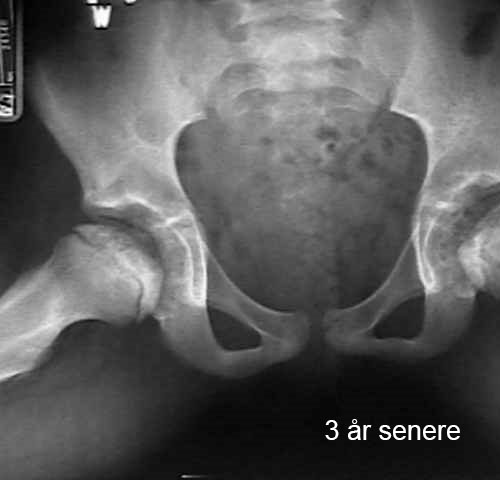

Lårbeinshodet dør delvis eller helt. Kroppen forsøker å løse dette ved å danne nytt beinvev og bryte ned det døde vevet. Det nye beinet er fortsatt svakt, noe som kan føre til at hoften mister sin runde form eller kollapser. Dette fører til deformasjon av hofteleddet. Bildene viser utviklingen av hoften hos et barn med Calvé-Legg-Perthes sykdom.